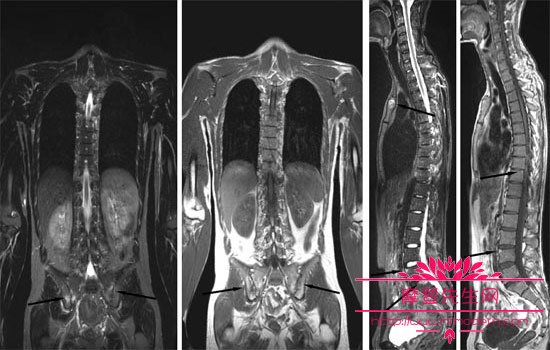

周杰伦患的是一种名叫强直性脊柱炎的疾病。这种疾病在民间被戏称为“不死的癌症”,寿命是不影响,但是生活质量比较差。南京鼓楼医院骨科主任邱勇教授坦言,虽然这样的称呼有些夸张,但如果不进行正规治疗,对健康损伤极大,最终造成家庭破裂的例子也不少见。因为《甄嬛传》而再次红极一时的“娘娘”蔡少芬、被人尊称为“周董”的周杰伦等,都是“强直性脊柱炎”患者,疼痛感不仅让他们生活质量遭受严重影响,甚至面临瘫痪可能。

强直性脊柱炎是一种自身免疫性疾病,男性患者居多,男女比例为9:1,也就是说,10个患者中9个是男性,其好发于15-25岁的年轻男子,10多岁的青少年也有发病。患者刚发病时,常常表现为腰背部疼痛,早晨起床后出现晨僵现象,活动后消失。由于早期症状不典型,常常不被重视而延误病情,等到不能抬头、低头,无法下蹲,甚至驼背,已进入中晚期,影响了生活质量。